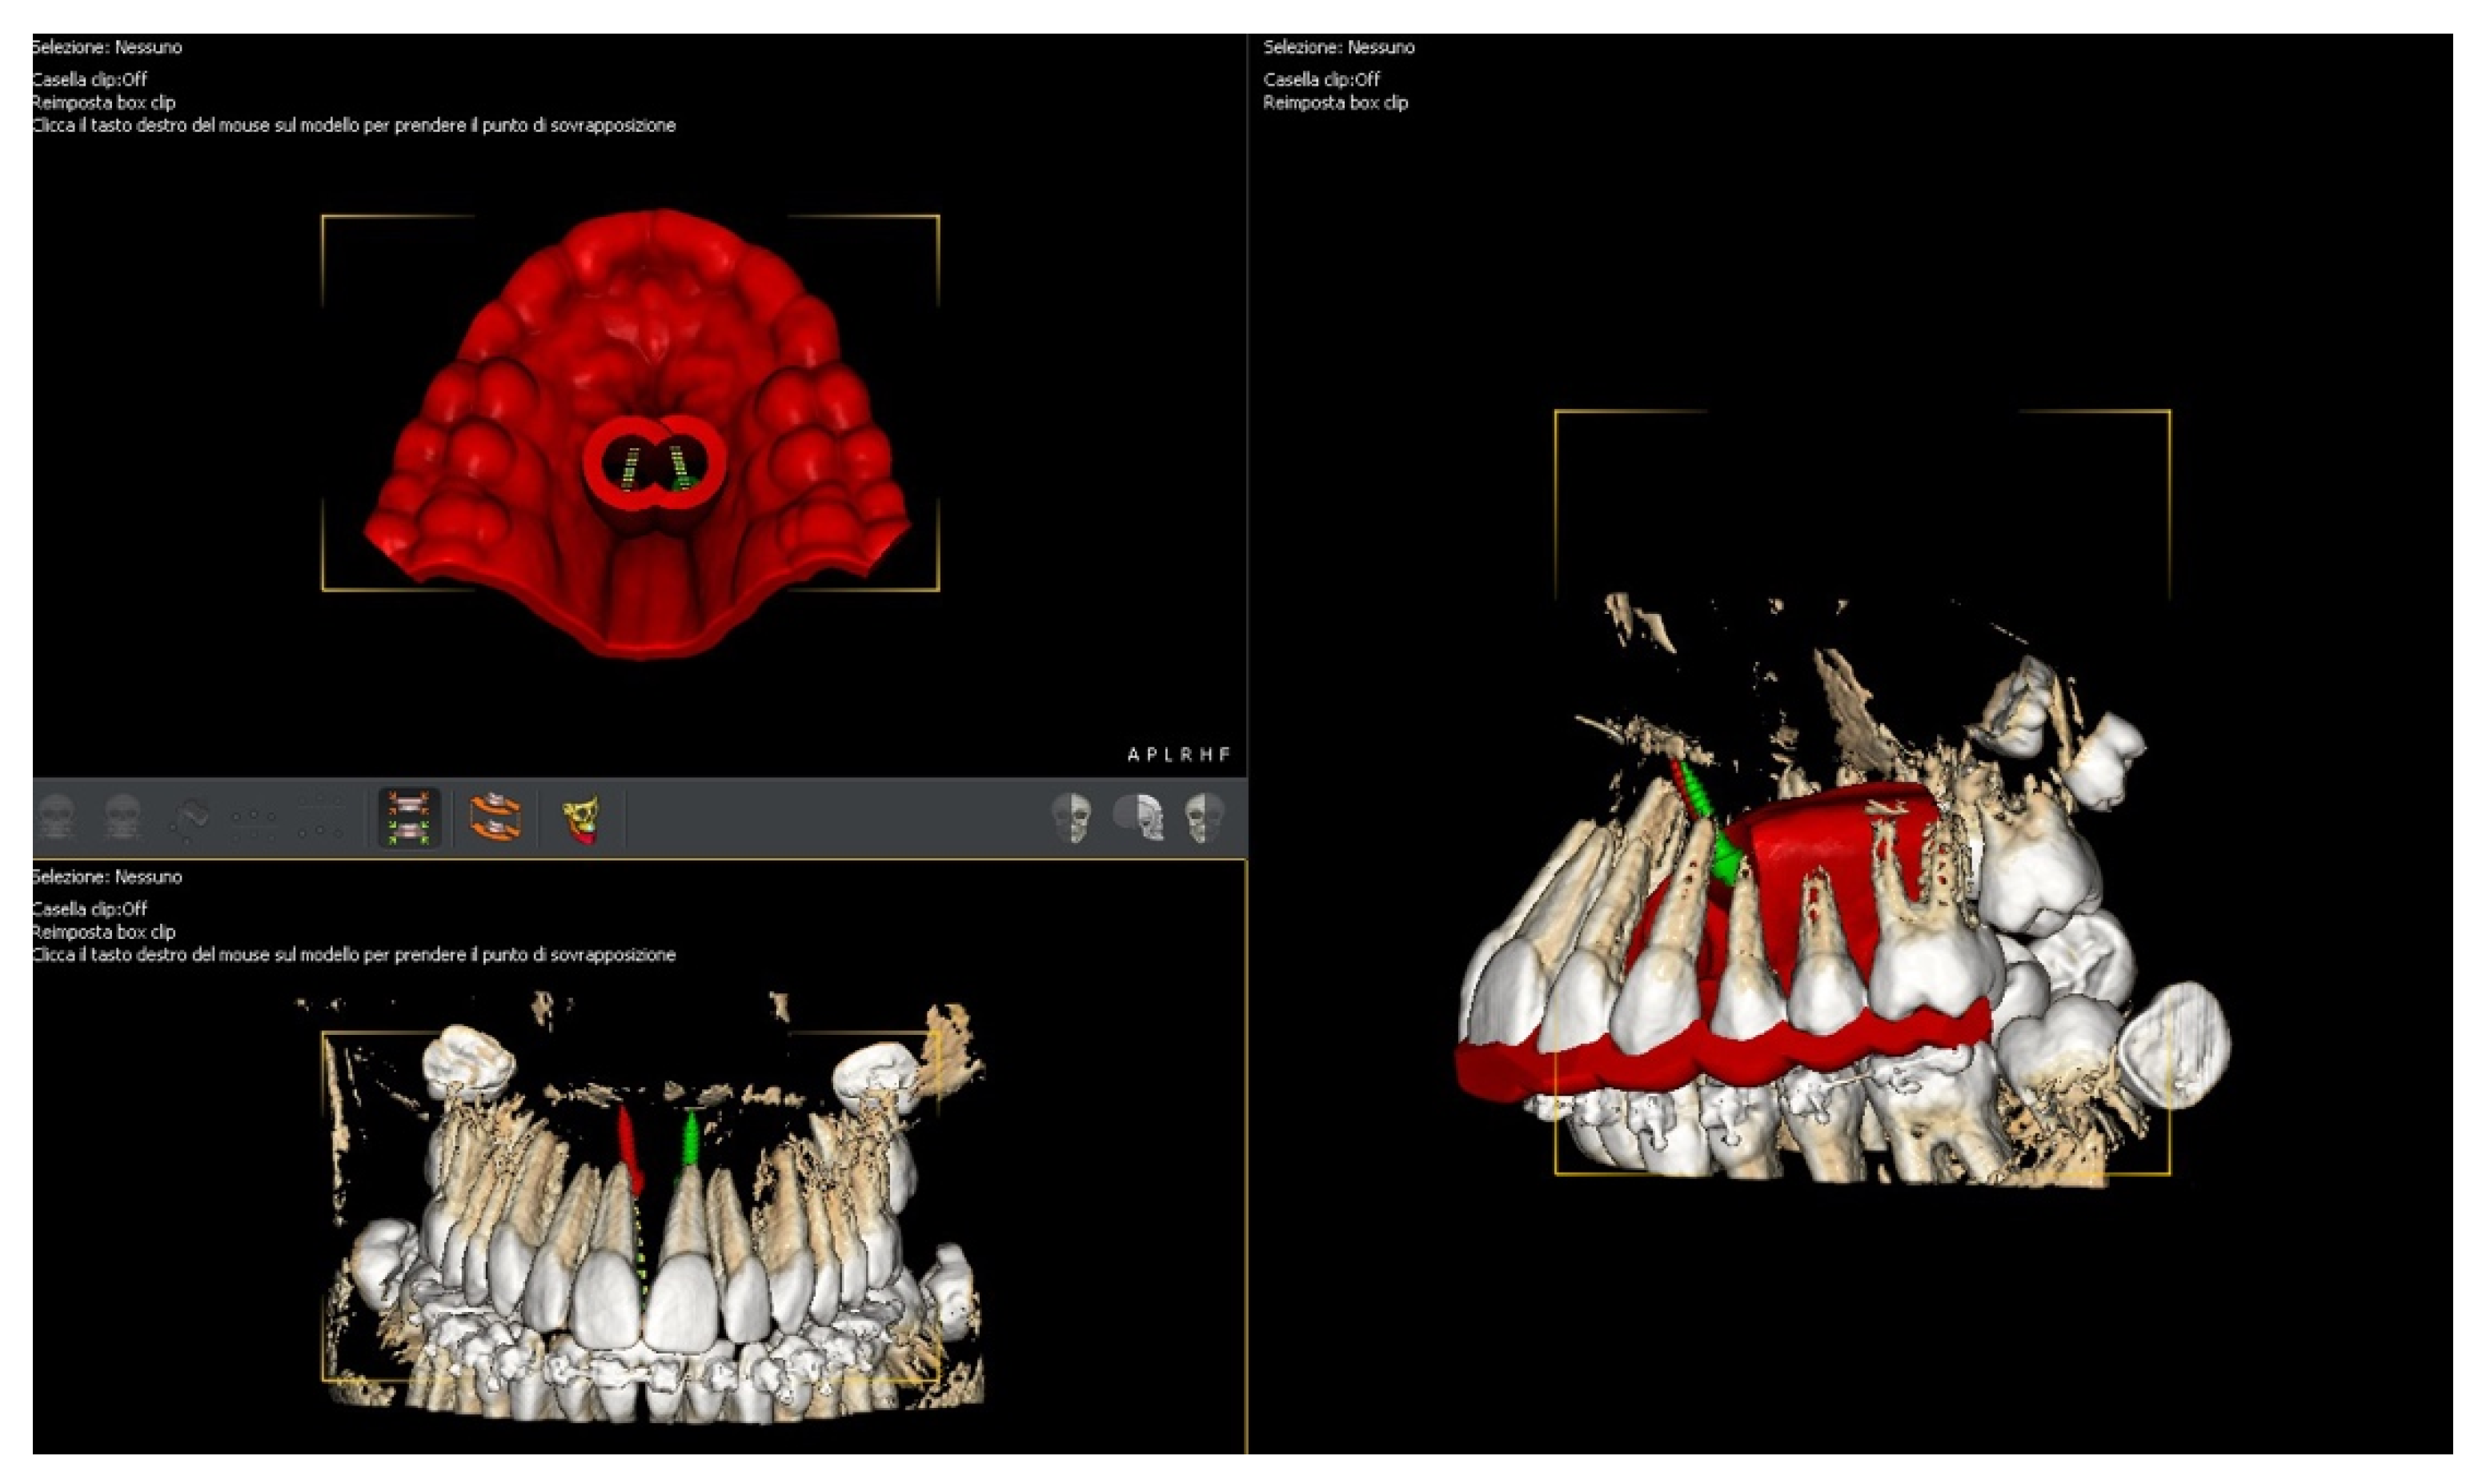

4.3. Treatment Strategy

4.4. Treatment Progress